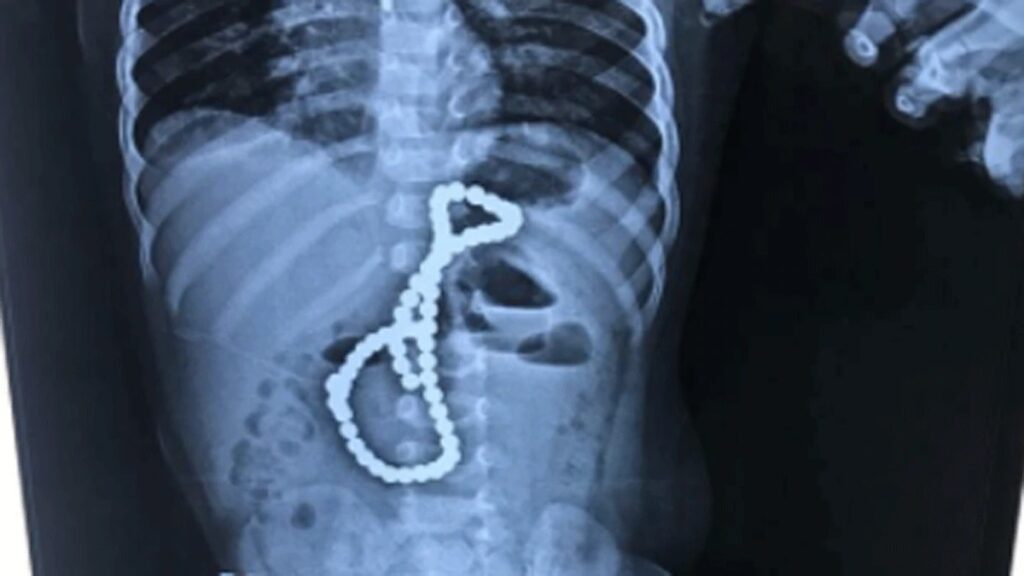

• डेढ़ साल का बच्‍चा निगल गया चुंबक की 65 गोलियां, तब ऐसे बची उसकी जान...

लखनऊ । उत्‍तर प्रदेश की राजधानी लखनऊ (Lucknow, capital of Uttar Pradesh) में एक डेढ़ साल के बच्चे के चुंबक की गोलियां (half year child swallowed 65 pills of magnet) निगलने का मामला सामने आया है. यहां खेलने के दौरान यह बालक चुंबक की 65 गोलियों को एक-एक करके निगल लिया. बच्चे को लगातार उल्टी […]